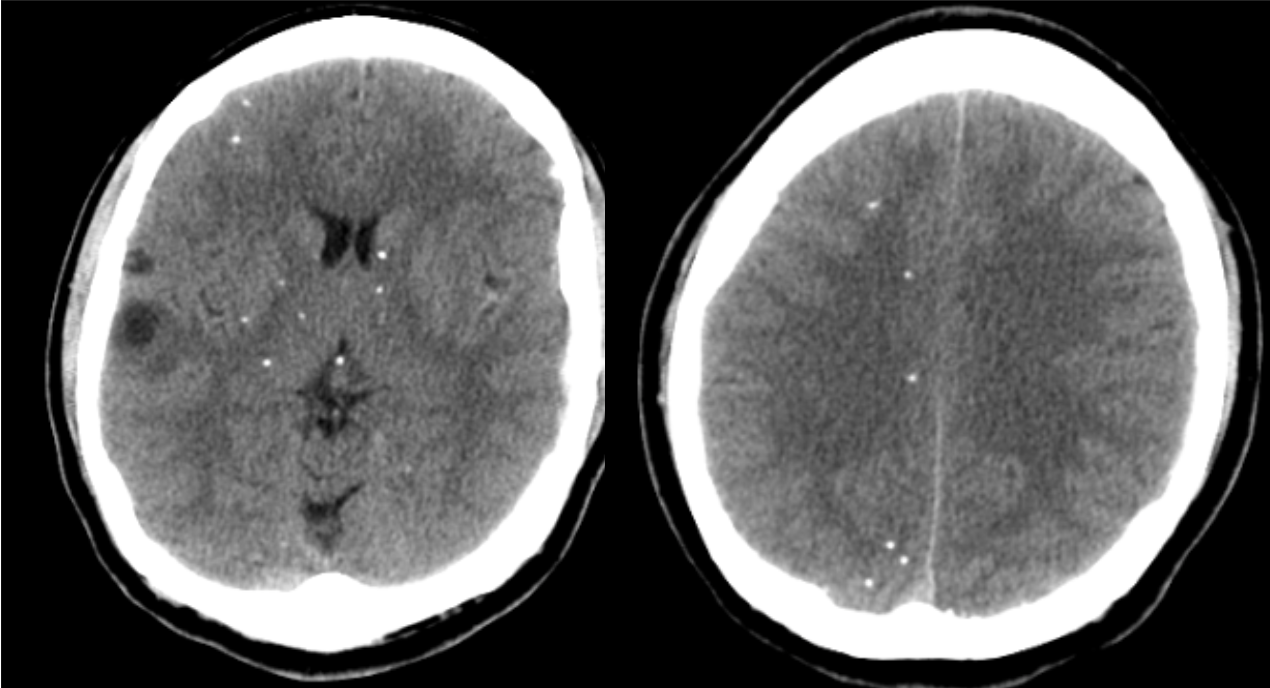

A 34 year-old man from Mexico presented with a long history of seizures.

Neurocysticercosis